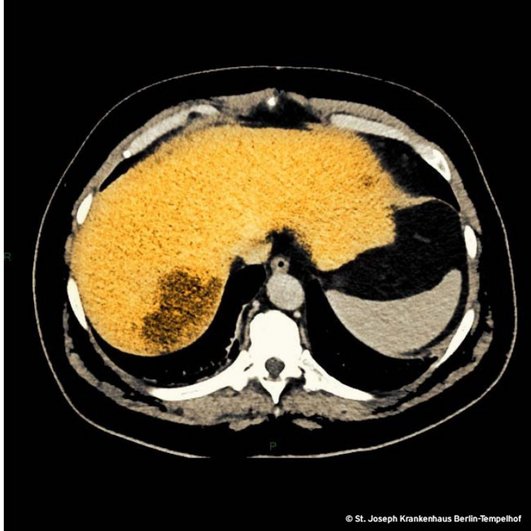

Die Kuh war vom Eis. Zwei Tage später haben wir die Schnittbildgebung des Abdomens wiederholt, weil die Bauchschmerzen die einzige klinische Fährte waren, der wir folgen konnten (unser Bild). Aus dem Inzidentalom ist ein einschmelzender Herd geworden, den wir drainierten. Es lag nahe, an einen Leberabszess, verursacht durch eine hypervirulente Klebsiella pneumoniae zu denken (siehe Infektoskop vom 01.08.2020) aber die Blutkulturen waren am Tag zwei ohne Wachstum und am Tag drei immer noch ohne Wachstum, und auch aus dem Abszesspunktat ließ sich kulturell kein Erreger nachweisen. Klebsiella pneumoniae hätten wir sicher gefunden. Irgendetwas fehlte noch, um die Geschichte plausibel zu machen. Gespräche mit Patientinnen und Patienten sind immer hilfreich wie auch hier. In der ersten Anamnese war verloren gegangen, dass er sich einen Tag bevor das Fieber begann die Zähne professionell hat reinigen lassen. Niemand hat danach gefragt und auch er hielt diese Information nicht für erwähnenswert.